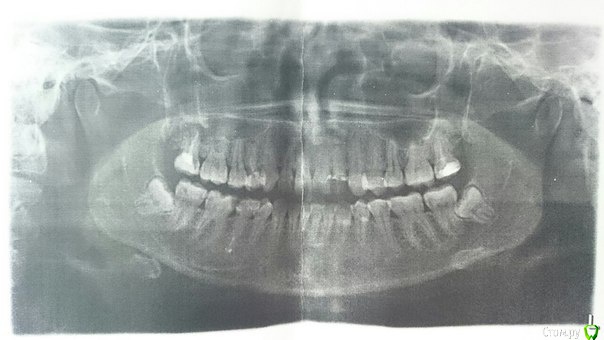

Хомячок Опубликовано 30 января, 2015 Автор Поделиться Опубликовано 30 января, 2015 За снимок отдала 700 руб, мне его распечатали на обычной бумажке, поэтому просто сфотографировала... Я пока новичок на форуме, пока не понимаю как тут врача найти Ссылка на комментарий

Хомячок Опубликовано 31 января, 2015 Автор Поделиться Опубликовано 31 января, 2015 заберите снимок в электронном виде, его могут например выслать на электронную почту Большое спасибо, полезный совет! Я не знала, что так можно, позвонила в клинику, они мне на почту выслали снимок. Ссылка на комментарий

Хомячок Опубликовано 31 января, 2015 Автор Поделиться Опубликовано 31 января, 2015 выкладывайте через радикалhttp://forum.stom.ru/topic/1640-snimok-zubov/Я чуть ниже прикрепила в сообщении, так видно? Ссылка на комментарий

red_butler Опубликовано 31 января, 2015 Поделиться Опубликовано 31 января, 2015 Вы мне не подскажете, как в верхнем сообщении заменить снимок на нормальный? уже не получиться Я чуть ниже прикрепила в сообщении, так видно? так будет лучше http://s019.radikal.ru/i611/1501/a3/fabfadcebce8.jpg 2 Ссылка на комментарий